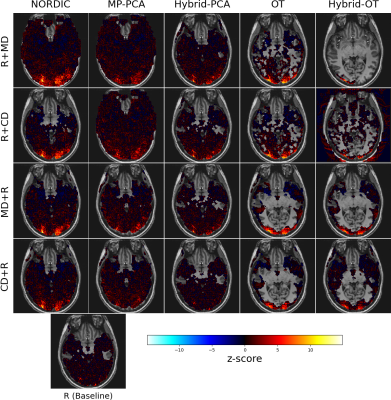

Figure 2 compares z-scores related to global effect of interest for a single subject. Denosing brings higher z-score in complex-valued or magnitude-only images. For the same subject, Figure 3 and 4 shows the denoised z-score maps for the 20 tested configuration and noisy baseline and the thresholded activations map respectively. OT method shows better performance than other methods, detecting activations only in gray matter, and yields highest z-score with largest spatial extend in occipital region, especially when doing magnitude-only denoising before realignment (scenario OT/MD+R It provides the best sensitivity/specificity trade-off.

Z-score spatial distribution for the same participant as Fig. 2. Only non zeros values are displayed. The Behavior of OT is more visible here: most of the z-score are zeroed out, and the remaining ones get higher values.

Zoom in the occipital cortex of z-score activation maps (axialslices) for the same participant as in Fig. 2 and 3 , thresholded at p < 0.05using FDR correction for multiple comparisons.